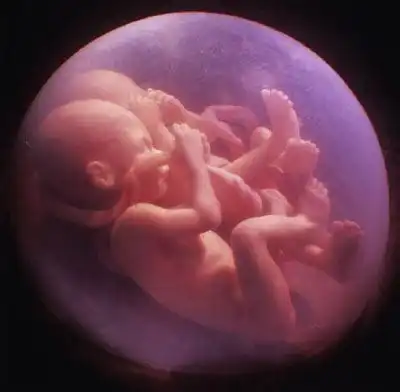

Сегодня жизнь близнецов начинают "контролировать" еще за долго до родов. И ученые пришли к удивительному выводу - близняшки общаются друг с другом еще в утробе матери!..

Вот этот снимок даже назвали "Поцелуй"...